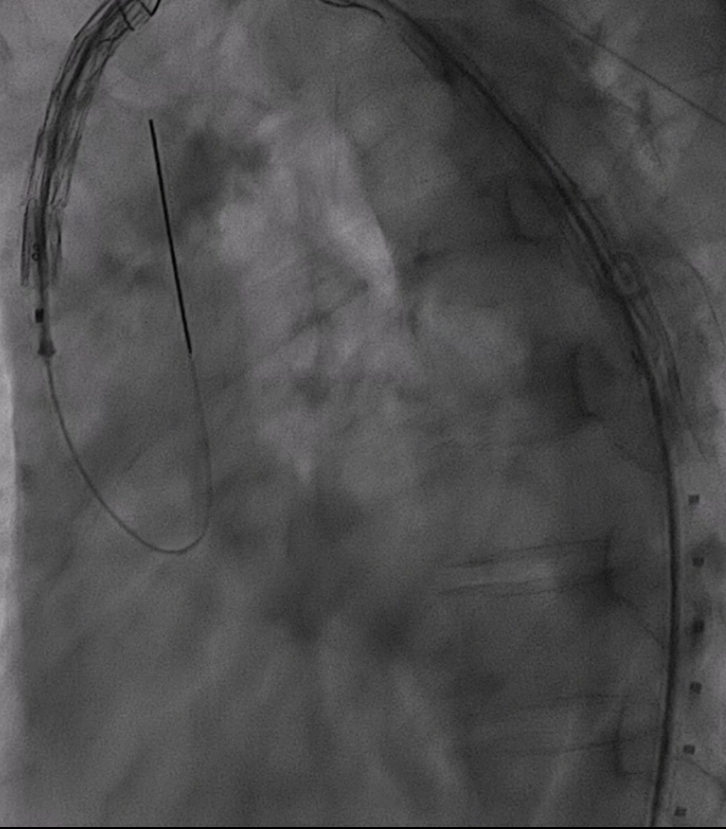

4. 支架输送与定位

根据详细测量数据,选用型号为 F46-40-45-191-16-14-14 FixTa一体化三分支主动脉覆膜支架支架系统。

将主导丝与导管准确卡入对应分线器卡槽内,撤出防缠绕导管内的导引导丝,各分支导管分别接入对应的分支导丝。主导丝连接支架输送系统,各牵引导丝从弓上引出并连接牵引器,通过牵引器保持适当张力,确保支架手柄编号与防缠绕导管手柄编号一致。

沿超硬导丝将主体缓慢送入主动脉弓部,透视下确保导丝无缠绕。

调整支架位置,确保主体分支支架对应无名动脉、左颈总动脉及左锁骨下动脉开口位置满意。